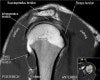

- Axial section

1) Anterior & posterior labrum

2) Subscapularis muscle & tendon

3) Biceps long head tendon

4) GH joint cartilage

5) Osseous structure

6) 관절액 있을때 FSE T2 FS에서 Labrum 선명, 관절액 없을때 FSE PD FS에서 Labrum 선명

- Sagittal section

1) T1WI : Rotator cuff muscle size, fat infiltration, Biceps tendinosis

2) T2WI : Rotator cuff insertion, edema, Rotator cuff partial or full thickness tear, Bursa fluid collection, Acromial type ,Glenoid fossa, Superior, middle, inferior GHL

근육 안에 tendon이 들어있다

원외부에서 SST와 IST가 겹침